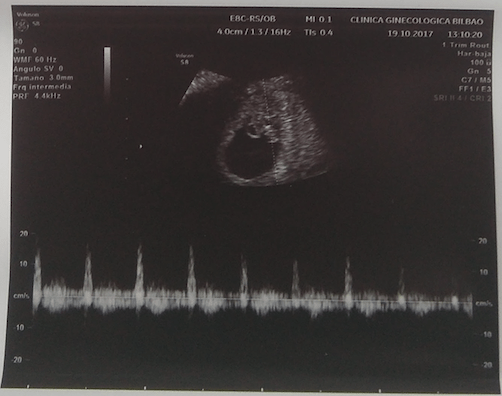

Hace dos días nos hicieron otra ecografía. Y a pesar de que ya quería a los dos, sólo había crecido uno, eso sí… ¡había crecido un montón! ¡Y su corazón latía a tope!, no se me olvidó el otro, pero me invadió de repente una relajación maravillosa: ¡¡está vivo!!

Un granito de arroz con un corazón que late fuerte